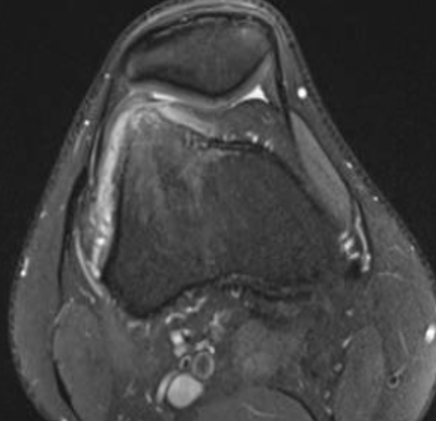

MRI

Osteoid osteoma femur